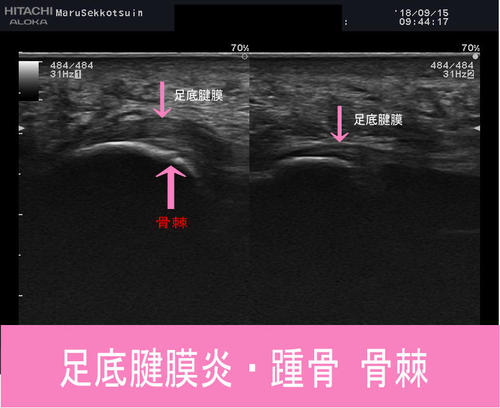

今回は触診、エコー検査にて、足底腱膜自体に緊張もなく、

後者の付着部に痛みが出ていたため「踵骨骨棘」と診断。